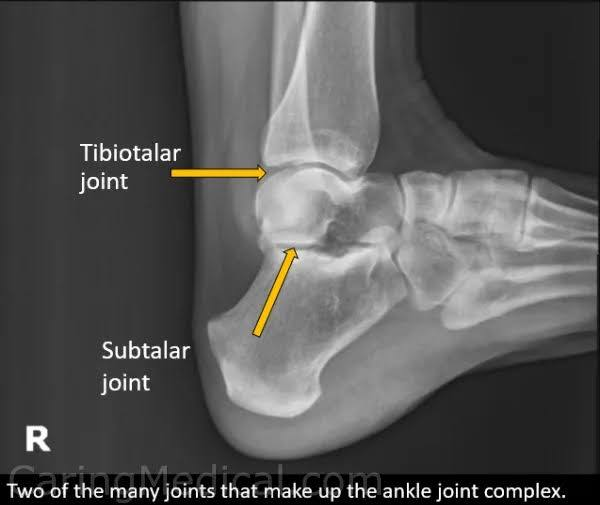

lateral ankle structures best demonstrated

Open tibiotalar joint

Trochlea of the talus

Distal tibia and fibula superimposed.

Lateral malleolus superimposed over posterior tibia and talus.

Tibiotalar Joint: joint classification / movements allowed

Diarthroidal hinge joint.

dorsiflexion and plantar flexion.